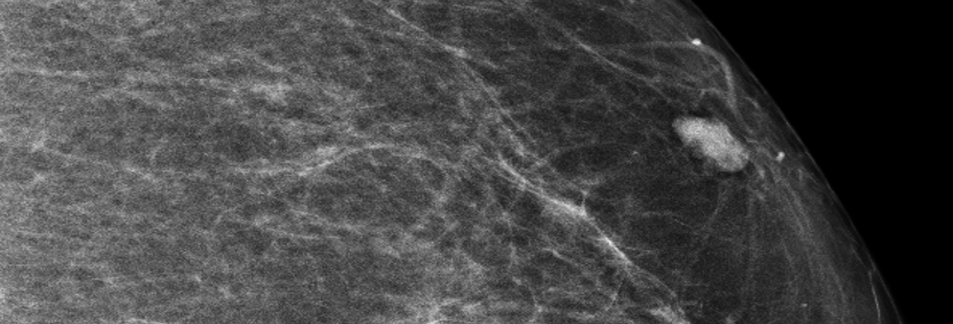

Un equipo de investigadores de la Universitat Politècnica de València y el Instituto de Física Corpuscular (IFIC), centro mixto de la Universitat de València y el Consejo Superior de Investigaciones Científicas (CSIC), ha sido seleccionado para la fase final del Digital Mammography DREAM Challenge (DM Challenge), un proyecto mundial impulsado por las principales instituciones de lucha contra el cáncer americanas, IBM y Amazon, cuyo objetivo final es mejorar la detección de cáncer de mama mediante la interpretación de la mamografía con técnicas de inteligencia artificial.

Según ha informado el IFIC en un comunicado, se trata también de reducir el número falsos positivos y evitar así la repetición de mamografías o pruebas invasivas innecesarias. En esta primera fase competitiva participaron más de 1.200 investigadores de todo el mundo repartidos en más de 120 equipos. El objetivo era identificar a los mejores grupos para continuar en la fase colaborativa. Sólo ocho han pasado a la final puntuando significativamente mejor que el resto, entre los que el equipo de la UPV-IFIC es el único representante español. El objetivo de los

finalistas ahora es construir un nuevo modelo, basado en avanzados algoritmos de predicción, que ayude a los profesionales médicos en el diagnóstico de esta patología.